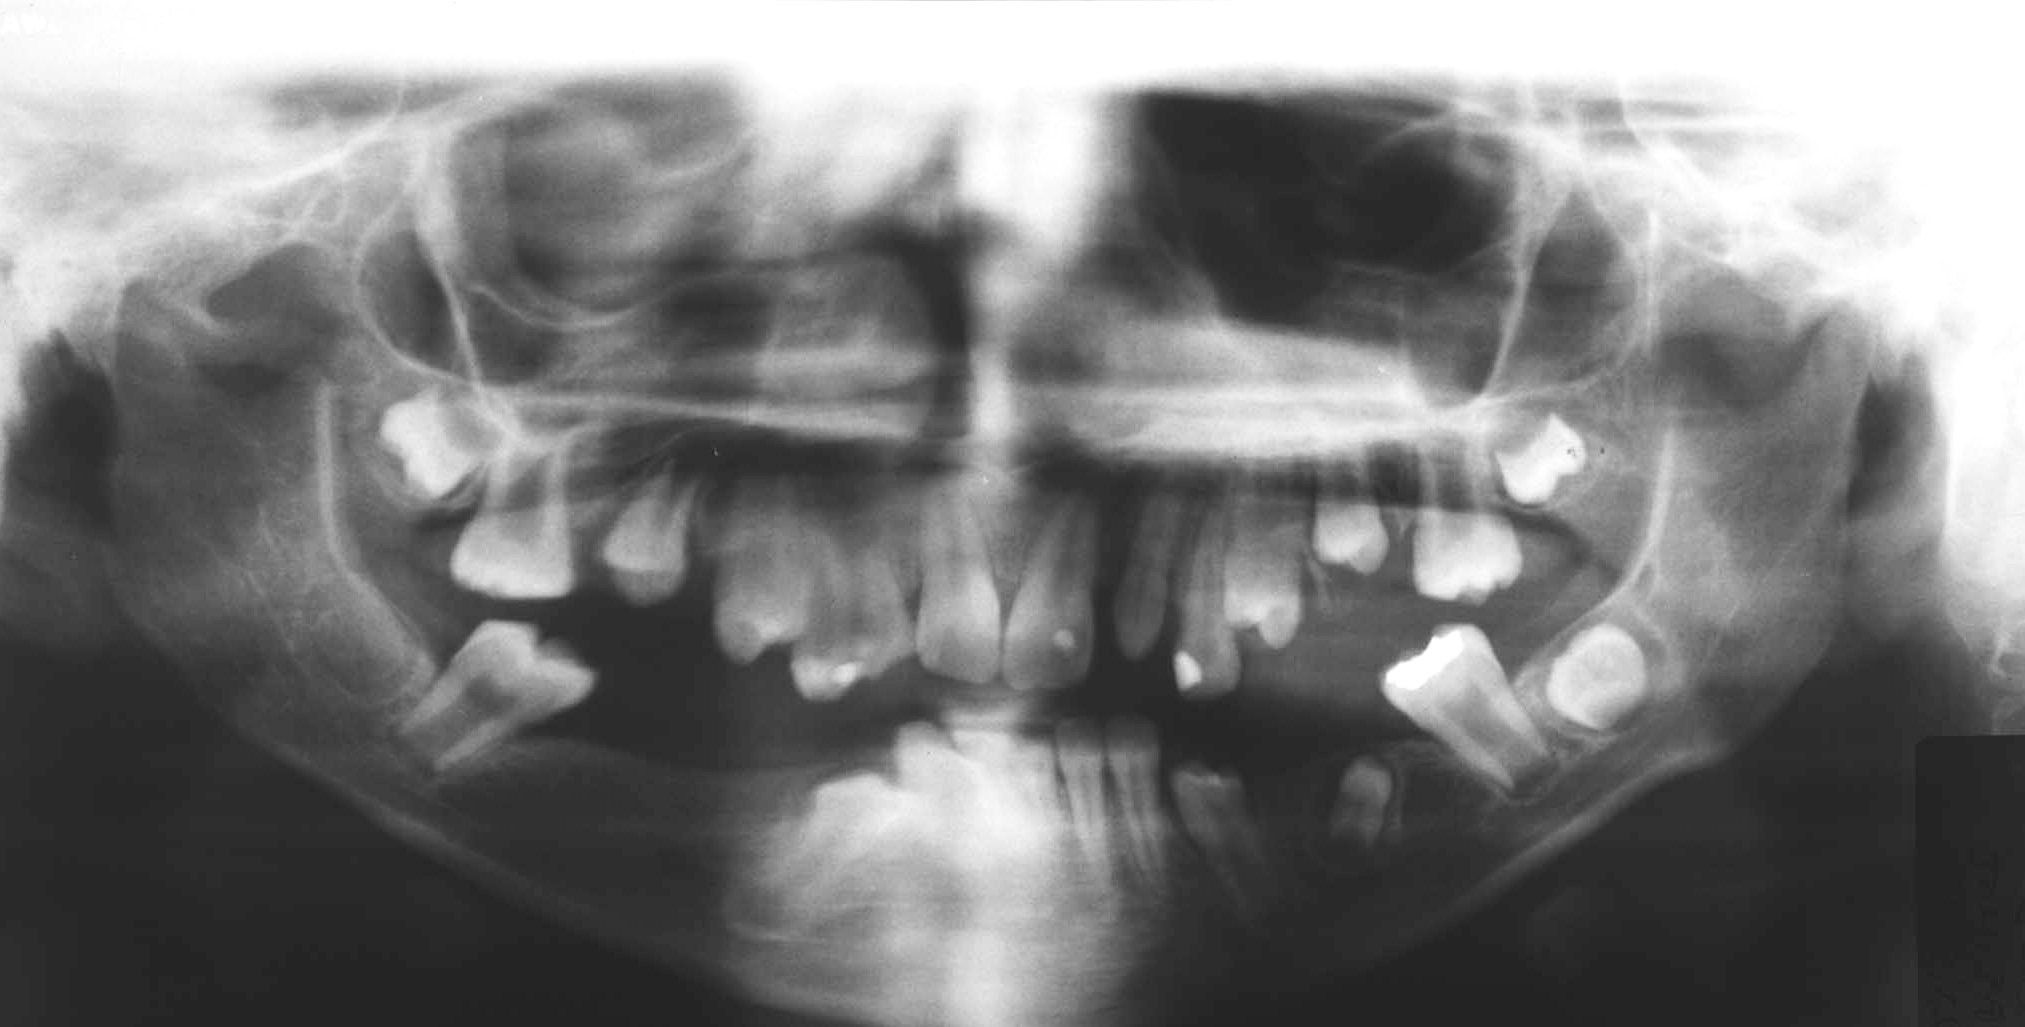

This paper presents a 12-year-old male patient with XXXXY syndrome, who was treated under general anesthesia twice due to mental retardation and uncooperative behavior. The general and dentofacial manifestations of XXXXY syndrome where present.The child had to be treated as as an emergency case both times due to severe pain and abcesses. Several teeth were severely decayed and had to be extracted that led to severe anodontia as there were no secondary dentition to follow. This case emphasises the importance of regular dental care, good nutricion and monitoring of dental development in children with XXXXY syndrome.